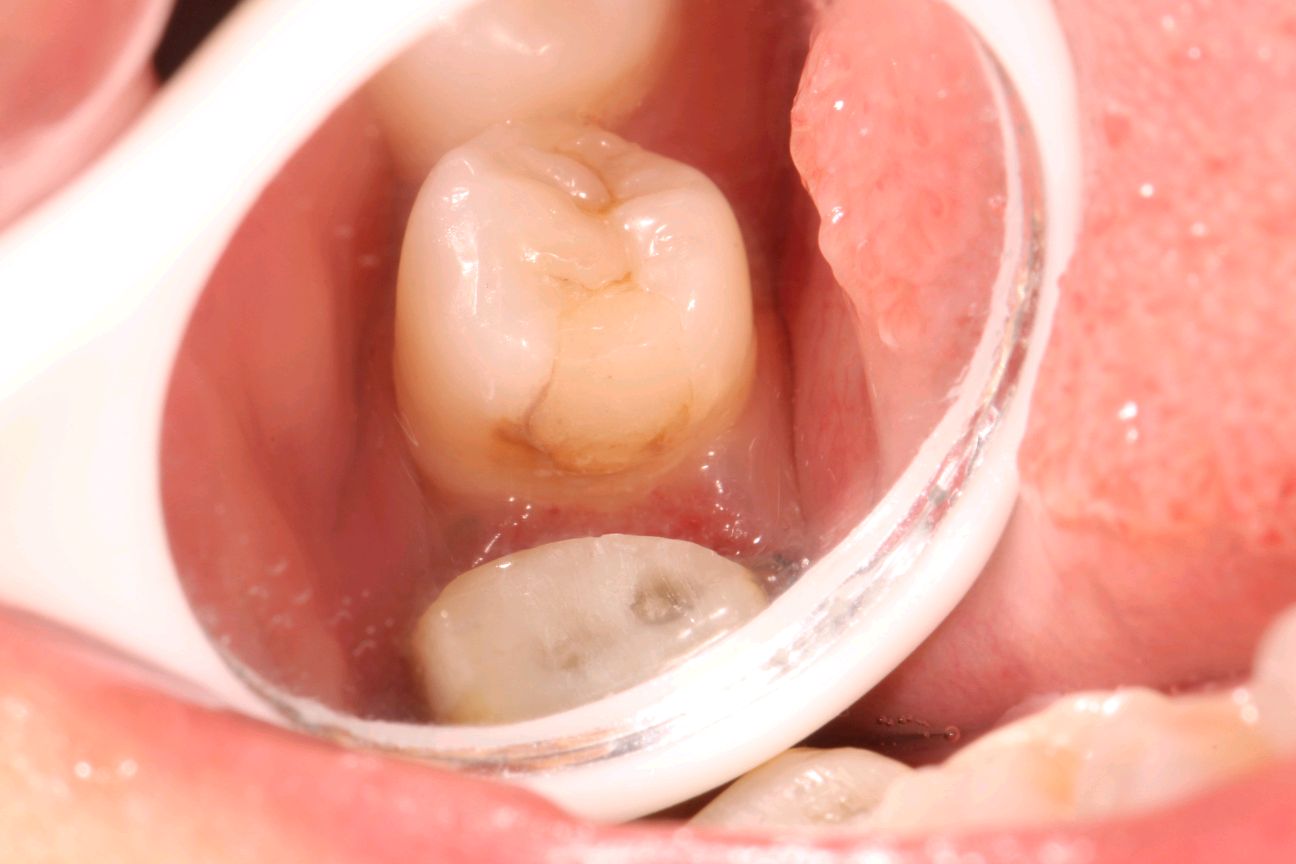

术中拆冠后

进行 46 牙 纤维桩植入,45 牙旧充填物去除